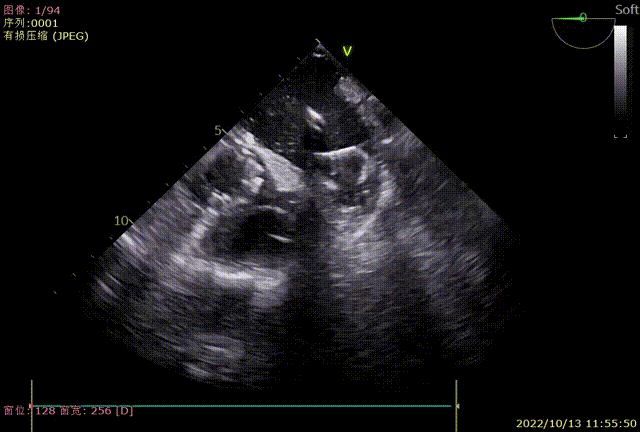

术中TEE各角度检查左心耳